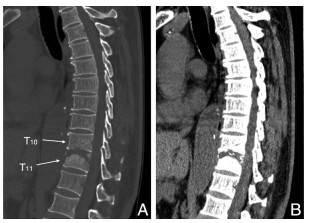

本文报道1例罕见的老年胸椎多发骨嗜酸性肉芽肿(eosinophilic granuloma, EG)病例。患者男性,66岁,因“腰背疼痛伴乏力两年余,加重三个月”就诊。经糖皮质激素联合免疫抑制保守治疗后临床表现及实验室检查好转,病理活检显示肉芽肿组织消失,后因病变部位出现压缩性骨折行外科手术治疗。该病例提示糖皮质激素联合环磷酰胺治疗成人多部位骨嗜酸性肉芽肿患者是可行的。